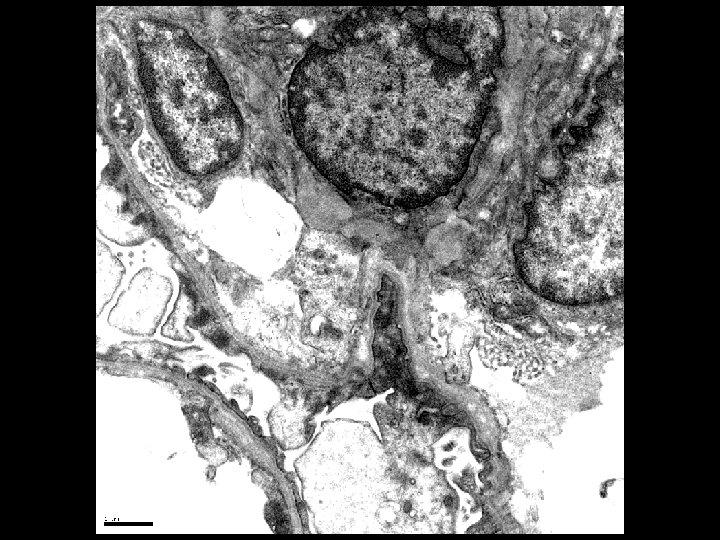

Electron Microscopy • Lamellation, thickening and thinning of GBMs

Alport’s Syndrome • Recurrent hematuria • Nerve deafness • Usually presents in early 20’s • Classic renal biopsy features by EM – Thickened and Thinned GBM – Lamination and Rarefaction – Grains